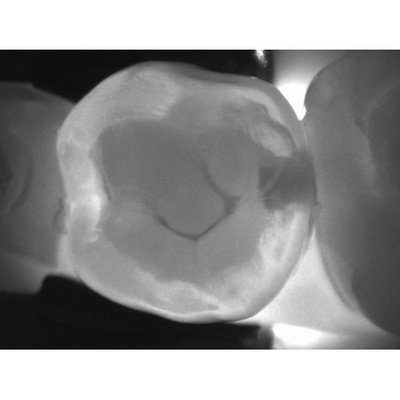

DIAGNOcam je první kamerový systém, který používá přímo samotnou strukturu zubu k diagnostice kazu (technologie DIFOTI).Zub je prosvícen světlem o specifické vlnové délce a je tedy sám použit jako světelný vodič. Digitální kamera při tomto prosvícení pořizuje záznam, který se zobrazí na obrazovce počítače. Zubní kazy a praskliny se tak projeví jako tmavé stíny. Díky své technologii DIFOTI (Digital Imaging Fiberoptic Transillumination) DIAGNOcam nabízí vysokou diagnostickou bezpečnost, která je v mnoha případech srovnatelná nebo i lepší než při použití RTG, zejména s ohledem na aproximální a okluzní kazy. Kromě toho je možné zobrazit některé druhy sekundárních kazů a praskliny.Jeho zásadní výhodou je možnost detekovat kazy již v počátečním stadiu a také zhodnotit, jak daleko kaz postoupil. Zda se ještě nachází ve sklovinné části, či již zasahuje do dentinu.